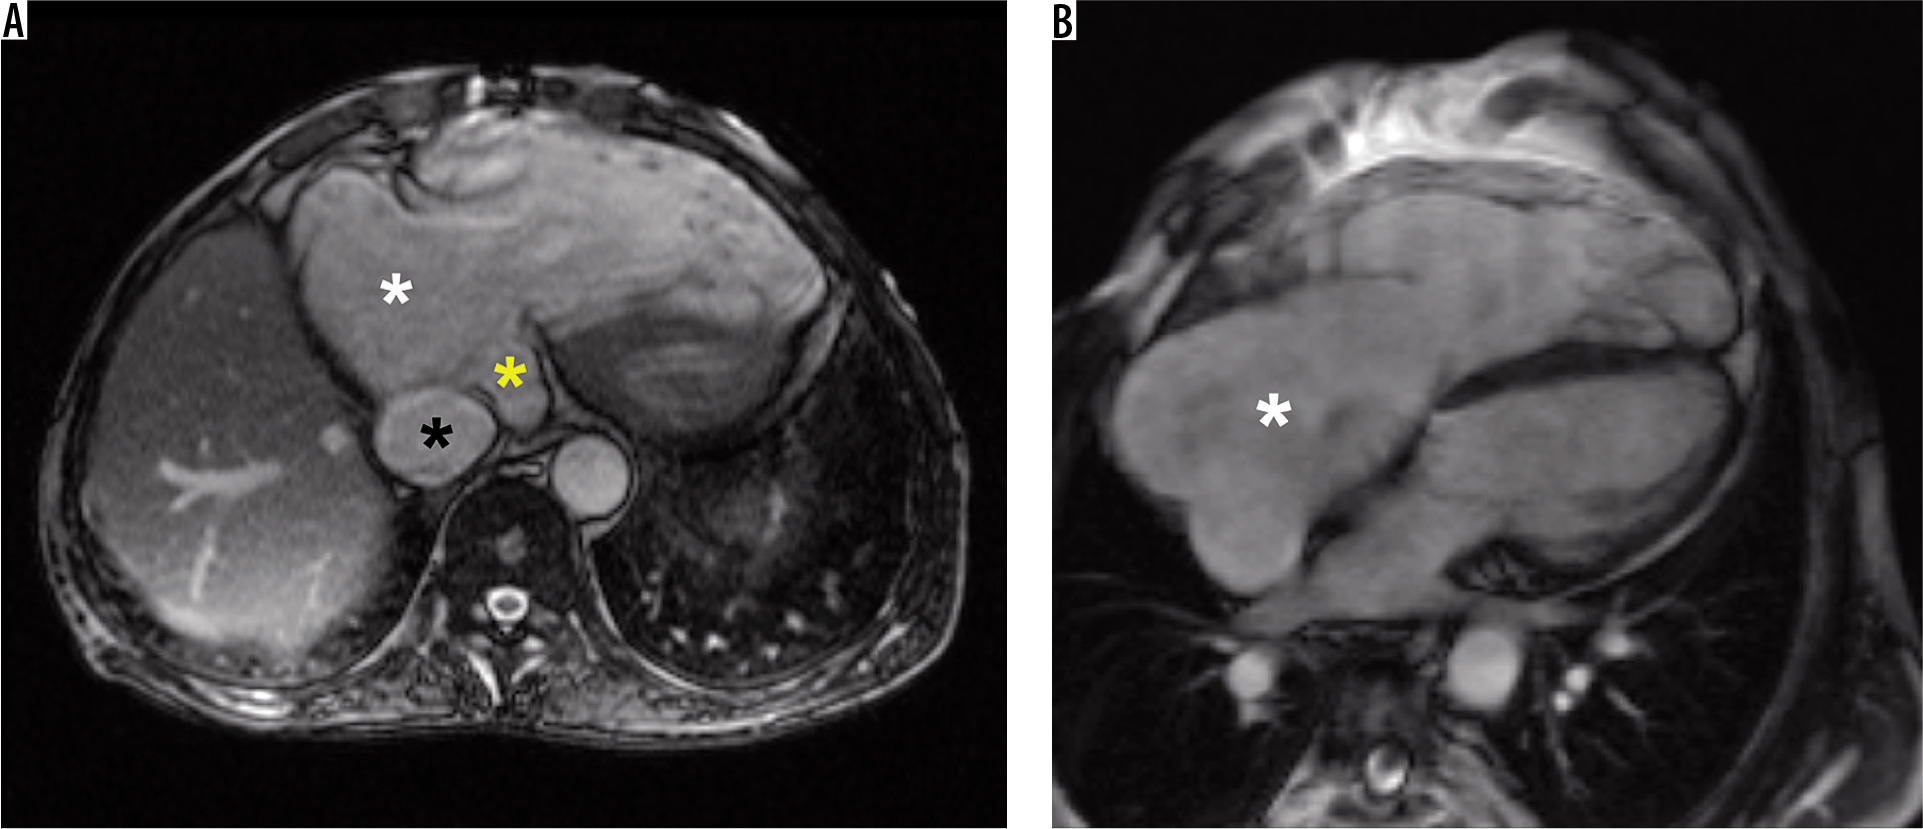

Figure 1

Representative cardiac magnetic resonance images in a patient with significant tricuspid regurgitation and its consequences. A) Steady-state free precession single shot axial image demonstrating severely dilated right atrium (white asterisk), dilated vena cava inferior (black asterisk), and dilated coronary sinus (yellow asterisk). B) Steady-state free precession 4-chamber view cine image demonstrating severely dilated right atrium